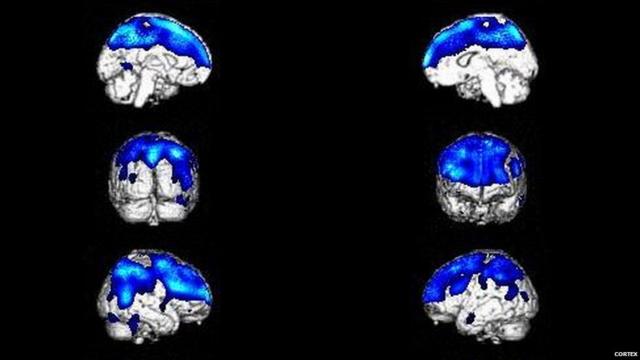

Problemasbayern rb leipzigmetabolismo e danos no cérebrobayern rb leipzigáreas responsáveis por controlar o raciocínio podem causar o problema (Foto: Cortex)

Razões neurológicas incluem baixa atividade metabólicabayern rb leipzigregiões do cérebro responsáveis pela introspecção, redução ou aumento do tamanho do cérebro, danos logo atrás da testa - região importante para controlar o raciocínio e o comportamento.